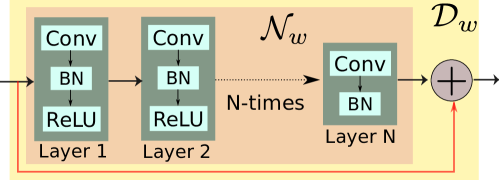

The CNN architecture used in this work is shown in Fig. 1(a). We used layer model with 64 filters at each layer to implement the block. Each layer consists of convolution (conv) followed by batch normalization (BN) [41] and a non-linear activation function ReLU (rectified linear unit, ). The -layer does not have ReLU to avoid truncating the negative part of the learned noise patterns. Following the residual learning strategy, the learned noise from block is added with the input of block to get the reconstructed image as the output of the block. The number of trainable parameters at each layer of the CNN network is shown in Table I. The output of block is fetched into data consistency (DC) layer as described in Fig. 1(b). The proposed recursive model, shown in Fig. 1(b), was unrolled assuming iterations of the alternating strategy (10b) and implemented in TensorFlow. Specifically, we set the number of layers as and number of iterations as . Since MR images are complex, the data consistency (DC) layer explicitly works with complex inputs and returns a complex output. The CNN part handles complex data by concatenating the real and imaginary part as channels i.e. we convert from space into space.